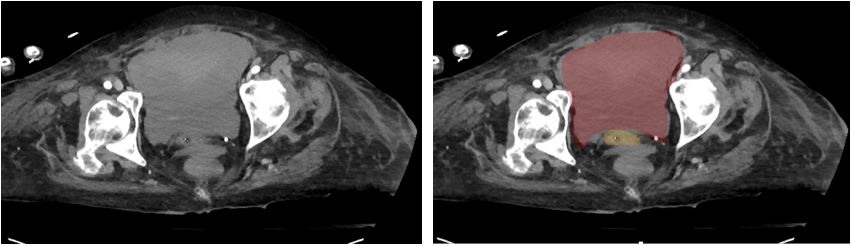

A 78-year-old female with a past medical history of recent CAD with NSTEMI and rectus sheath hematoma presented with severe abdominal pain via EMS. In transport, the highest heart rate was 35, and the lowest blood pressure was 93mmHg systolic. The patient had been discharged from rehabilitation four days prior to presentation. She reported mild pain at discharge that acutely worsened on the day of presentation. While the patient was being volume resuscitated, a RUSH exam was performed that showed severely reduced LVEF and a distended bladder. A foley was placed and minimal urine came out. The patient’s blood pressure and heart rate improved, and she was transported to the CT scanner, where a large pelvic hematoma was identified. The patient was taken for ex-lap and admitted to the surgical ICU.

Figure 4. CT Abdomen and Pelvis. Red: Hematoma; Yellow: Bladder